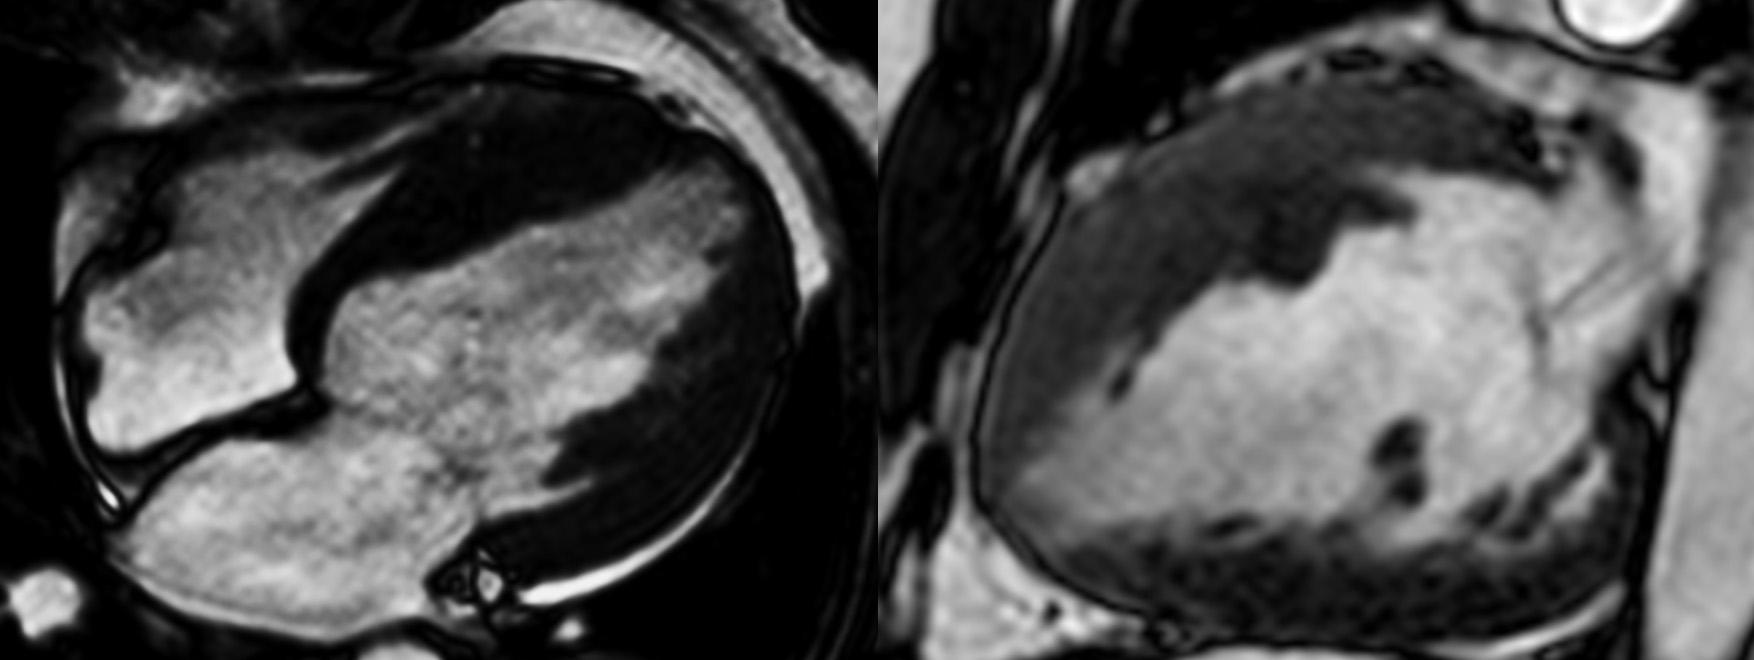

A Miocardiopatia Hipertrófica (MCH) é uma doença genética predominantemente autossômica dominante associada a aumento da morbidade e mortalidade. Caracteriza-se pelo aumento da massa cardíaca, decorre…